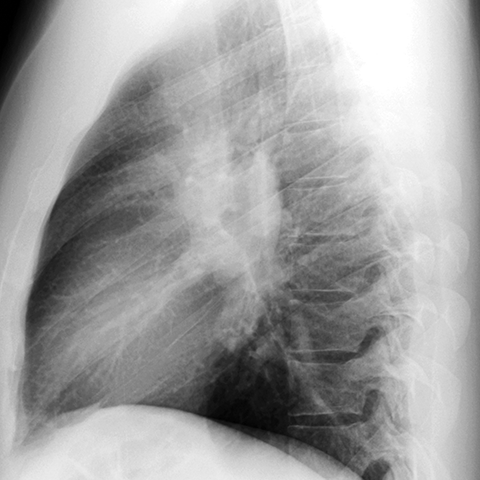

Hilar Nodes in Sarcoidosis [2 of 3]